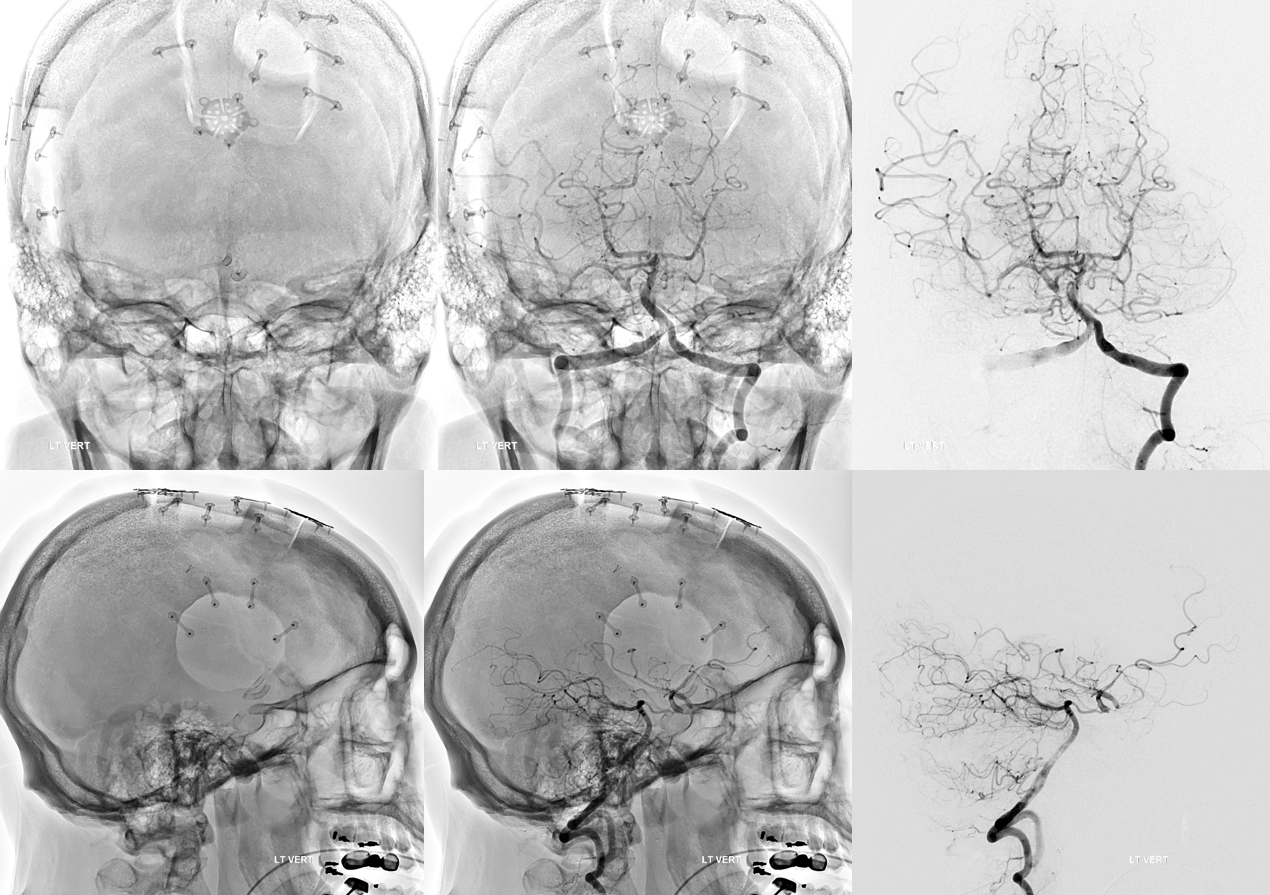

Angio intraop post bypass- STA-MCA working

ACA-ACA did not have flow at this point. Tested by a left A2 BTO. How does that test for bypass patency?

STA-MCA bypass, right ophthalmic, and right PCOM not enough to supply right ACA at this stage — tested by left supraclinoid bypass — what is the rationale there?

Stereo views of the two craniotomies, with translucent and sonolucent closure

Can we sac the ACOM now? Coil aneurysm and the ACOM? Why not? Can argue for that. We choose H-Flow Diversion. A1-A2 bilaterally. On the right, we have to access the A1-A2 via the PCOM. This is not a job for 27 or 21 catheter. Plan for Silk Vista Baby on right and Pipeline Shield on left